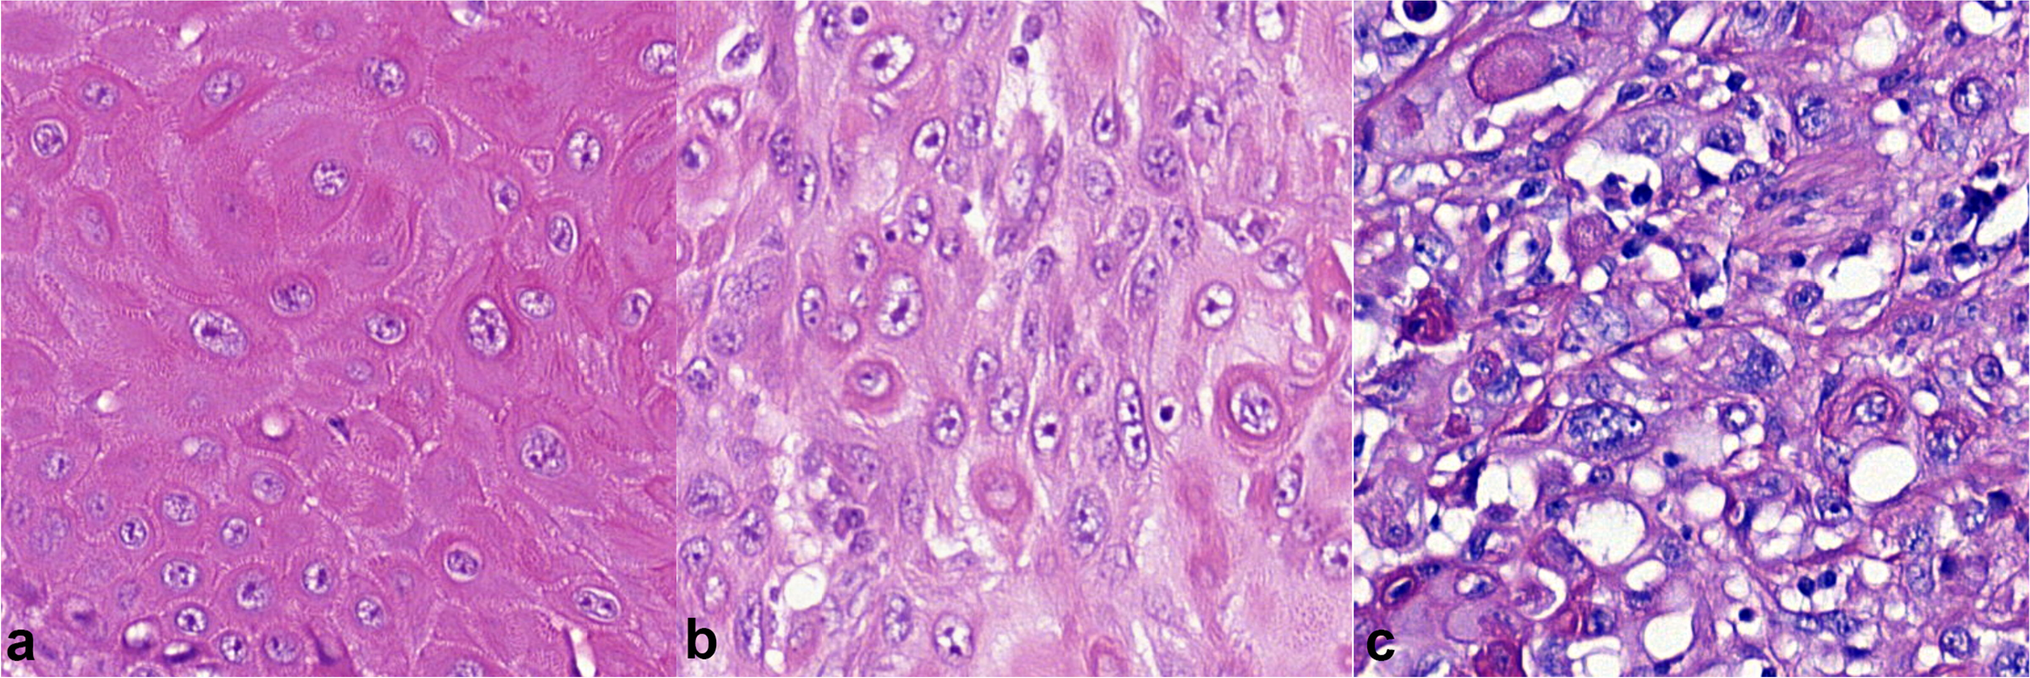

Fig. 2

Histopathologic grading of penile squamous cell carcinoma according to WHO recommendations: hematoxylin–eosin stain, magnification × 400. a Grade 1, b grade 2, c grade 3

Histological grade

The tumors were graded using a three-tiered system based on ISUP/WHO recommendations [17, 25]. In this system, grade 1 tumors are well differentiated with minimal cell atypia, and grade 3 tumors show no maturation and have a high cell pleomorphism and high mitotic activity. Tumors that do not meet the criteria for grades 1 or 3 belong to grade 2 (Fig. 2). Squamous cell carcinomas are usually heterogeneous and show different grades in different parts of the tumor; the histological grade is assigned based on the highest observed grade, as any proportion of high grade is relevant.